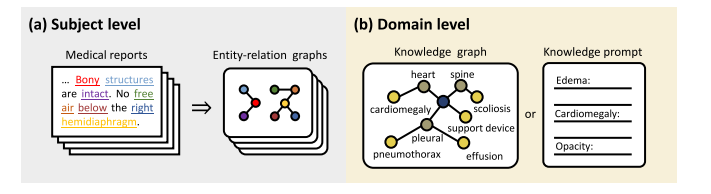

Fig. 9. Illustration of knowledge enhancement at different levels (with the chest X-ray as an example). (a) At the subject level, external knowledge aids in converting medicalreports into entity-relation graphs, which elucidate the causal relationships among medical entities in the report. (b) At the domain level, the domain knowledge is presented asa knowledge graph or descriptive knowledge prompt, directly providing human prior guidance for pre-training

图9:不同层面的知识增强示例(以胸部X光片为例)。(a)在主体层面,外部知识有助于将医学报告转化为实体-关系图,该图阐释了报告中医学实体之间的因果关系。(b)在领域层面,领域知识以知识图谱或描述性知识提示的形式呈现,直接为预训练提供人类先验指导。